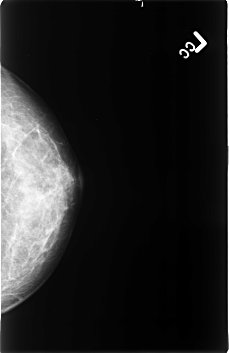

B_3403_1.LEFT_CC

LEFT_CC LINES 4584 PIXELS_PER_LINE 2968 BITS_PER_PIXEL 12 RESOLUTION 50 NON_OVERLAY

LEFT_MLO LINES 4496 PIXELS_PER_LINE 2968 BITS_PER_PIXEL 12 RESOLUTION 50 NON_OVERLAY